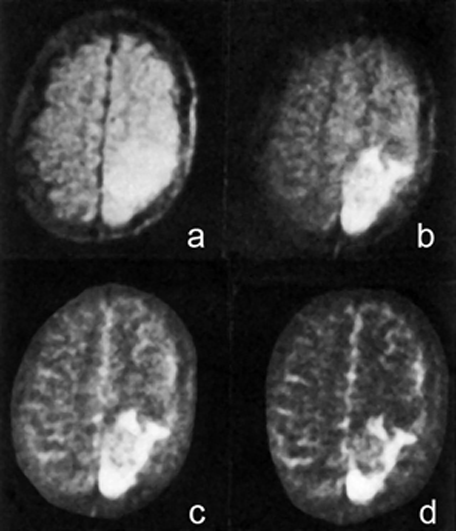

By 1982-1983, the Hammersmith and Wiesbaden groups pointed out that long hea­vi­ly T2-weighted multiecho SE se­quen­ces were better at highlighting pathology (Figure 20-43) [⇒ Bydder 1982; ⇒ Rinck 1983]. There were similar groups in Germany and in the United States, mostly in New England and California.

Figure 20-43:

Spin-echo images from 1984 of a recurrent brain tumor taken on a 0.14 Tesla system; TEs (a-d) bet­ween 20 and 300 ms.

Long echo times in multiecho CPMG se­quen­ces were a major leap forward in the first half of the 1980s. It took some years until T2-weighted images were gen­erally accepted, mostly because many com­­pa­­nies claimed that long TE was neither pos­sib­le nor neces­sary.

The images were made five years before the introduction of Gd-based contrast agents; the tumor can be best delineated on image (d) at a TE of 300 ms.

Illustration from: Rinck PA, Bydder GM, and Harms SE. Magnetic resonance imaging of the brain. Pub­­lish­ed in the first edi­tion of this textbook in 1985.